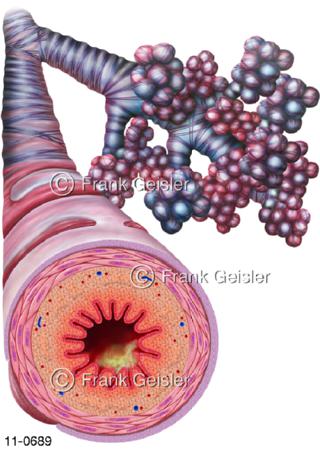

11-0689 Atemwege, Bronchien mit Asthma bronchiale